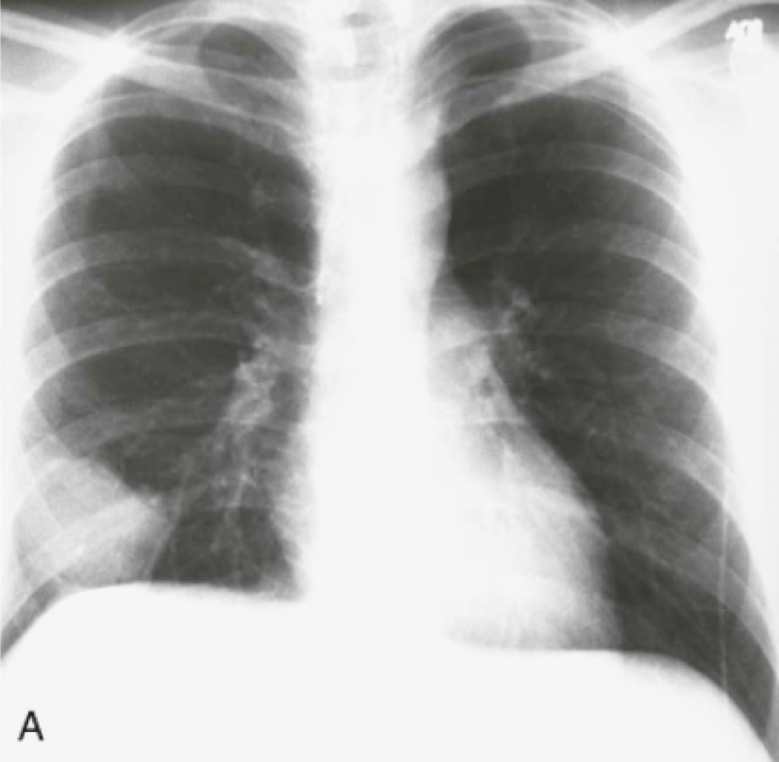

Question 24

Question

What does this CXR tell you?

Answer

• Hydropneumothorax

• Tension Pneumothorax

• Pneumomediastinum

• Pneumothorax